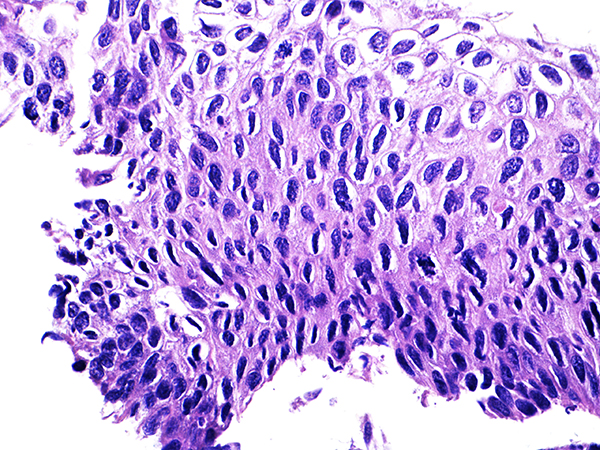

Area 1 - Soft Bx CIN 2 40x - High Power |

![]() Case 1